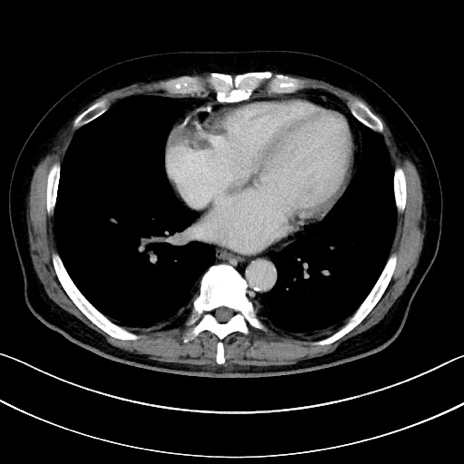

症例15(横断像)

【症例】70歳代男性

【主訴】腹痛

【現病歴】今朝から腹痛あり。全体的に痛い。特に左上の方。排ガスが今日はない。冷や汗が出る。

【既往歴】直腸癌術後

【身体所見】左側腹部〜上腹部に圧痛あり。腹膜刺激症状明らかなではない。軽度反跳痛。左下腹部に術後瘢痕あり。

【データ】WBC 7700、CRP 0.02